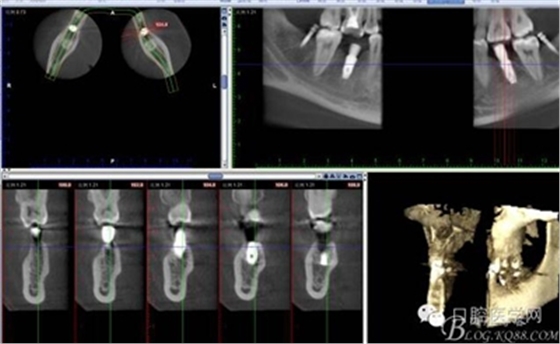

CT

拔除18 28 38 48 后 47 遠(yuǎn)中植入支抗釘

因?yàn)榛颊咭蟀朐聝?nèi)完成,所以同期植入韓國豋騰4.5*10mm種植體